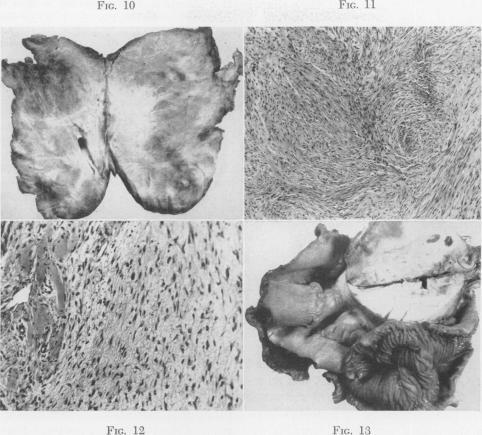

Dermal and fascial fibromatosis.

Ann Surg. 1954 Apr;139(4):453-67. doi: 10.1097/00000658-195404000-00009.